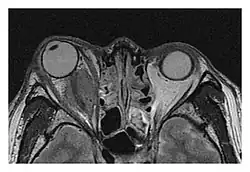

The extent of inflammation that can occur in IgG4-ROD is well demonstrated on magnetic resonance imaging (MRI).

Infraorbital nerve enlargement (IONE) is considered to be a particularly suspicious sign of IgG4-ROD, but seems to occur only when inflammation is in direct contact with the infraorbital canal.[10] IONE is defined as the infraorbital nerve diameter being greater than the optic nerve diameter in the coronal plane.

Enlargements in the left inferior rectus muscle and infraorbital nerve (arrow) in a 65-year-old man with a serum IgG4 of 404 mg/dL.[1] (T2-weighted MRI)